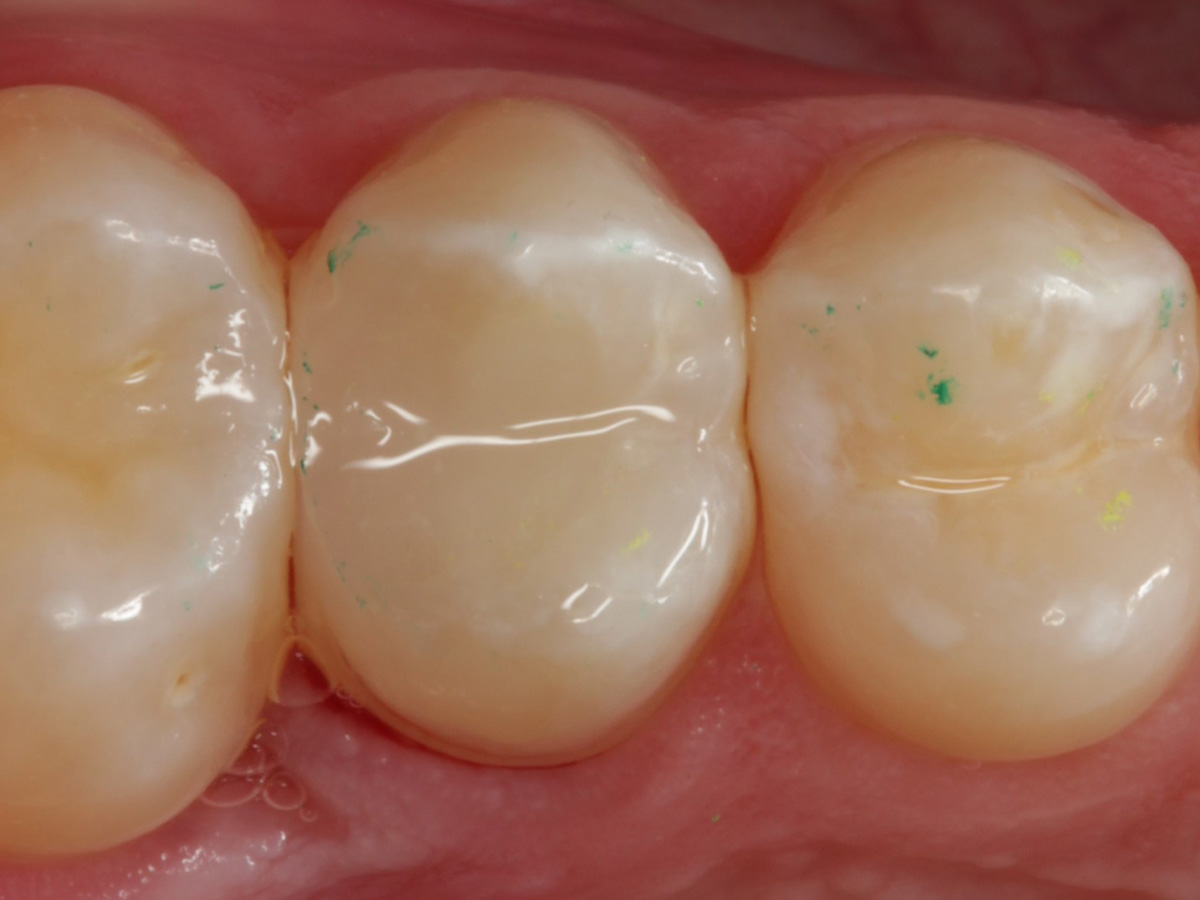

Abbildung 28

Kompositrestauration nach „Schachtverschluß“; keine Krone geplant

Abbildung 29